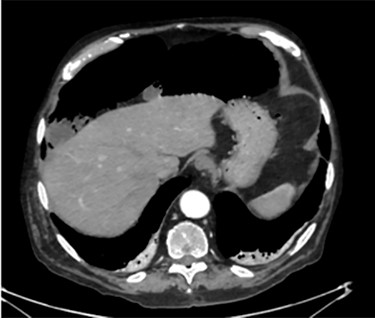

Unfortunately, once he returned home his temperature started to rise up to 38°C and he was readmitted to the hospital. A new contrast-enhanced Chest/Abdomen CT showed a bilateral pneumonia and a massive amount of intraperitoneal free gas, mainly in the abdominal upper quadrants (Fig. 2). No fat stranding, nondilated bowel, no vascular abnormalities and no free fluid were detected. Although the CT showed an evident worsening, the patient still remained completely asymptomatic on physical examination. Accordingly, he started to be treated with meropenem for pneumonia (Escherichia coli was isolated into the sputum) and he finally agreed to underwent diagnostic laparoscopy. Surprisingly, that was definitely not a case of pneumoperitoneum but an idiopathic PCI as we found multiple intramural air content cyst, about 2–3 cm in diameter, all around the small bowel loops and mesentery (Fig. 3). No intra-abdominal maneuvers were made. The patient had an unremarkable recovery (Clavien–Dindo classification grade was 1) [3] and he was discharged home on postoperative Day 15 in well condition, once he had recovered from pneumonia.

Intra-operatory findings of pneumatosis cystoides intestinalis of the small bowel.